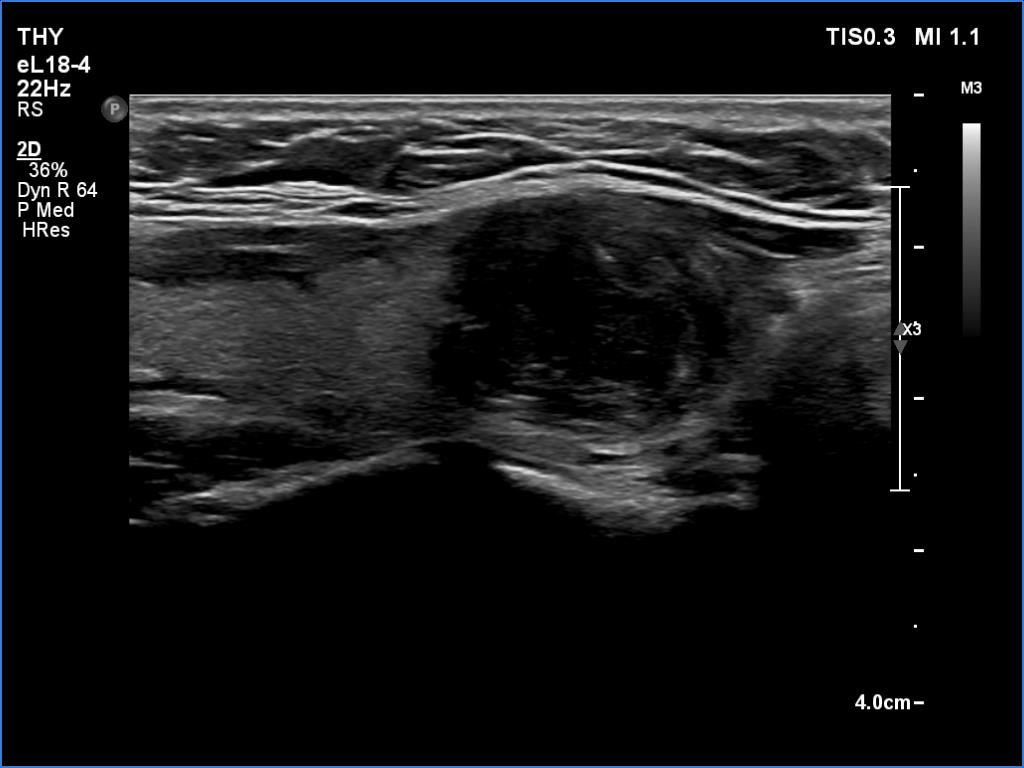

Ultrasonography revealed an echonormal thyroid. There was dominantly moderately hypoechoic nodule in the right lobe. Some parts of the lesion were deeply hypoechoic, and a few small cystic chambers were also within. The nodule presented with irregular shape and borders and had intranodular echogenic figures, primarily granules.

It is ambiguous how to interpret the echogenic figures. Although the presence of irregular shape and borders increases the likelihood that the echogenic granules are indeed microcalcifications, comet-tail artifacts must be also considered.

It is worth comparing the images recorded by using different settings. By using harmonization, we lose the details of very hypoechoic areas. Essentially, the latter seem to be anechoic.